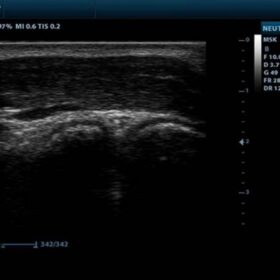

Ultrasound Mindray DP-10 – Image Gallery